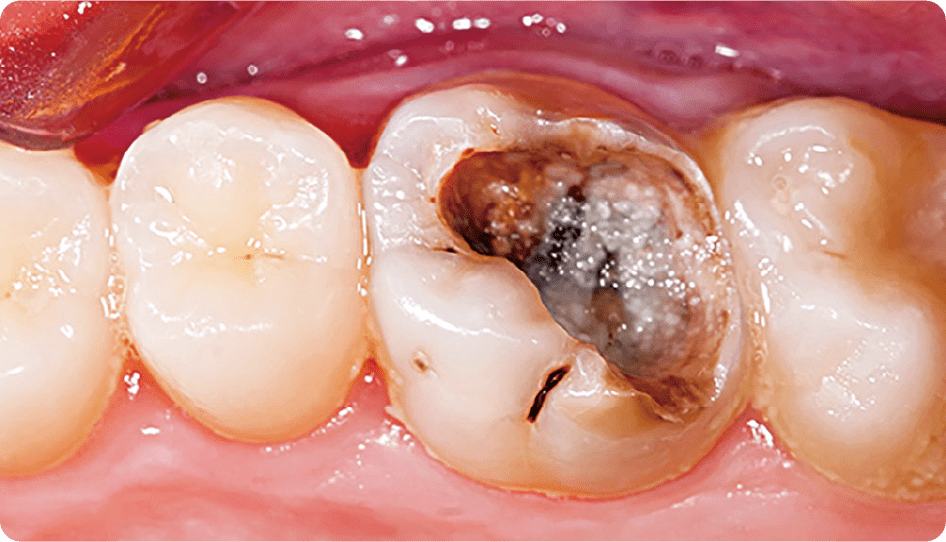

むし歯菌によって歯に穴があくこの病気は、むし歯菌×糖分×時間×歯の質のバランスが崩れることで発症します。定期健診で早期発見、予防することが大切です。